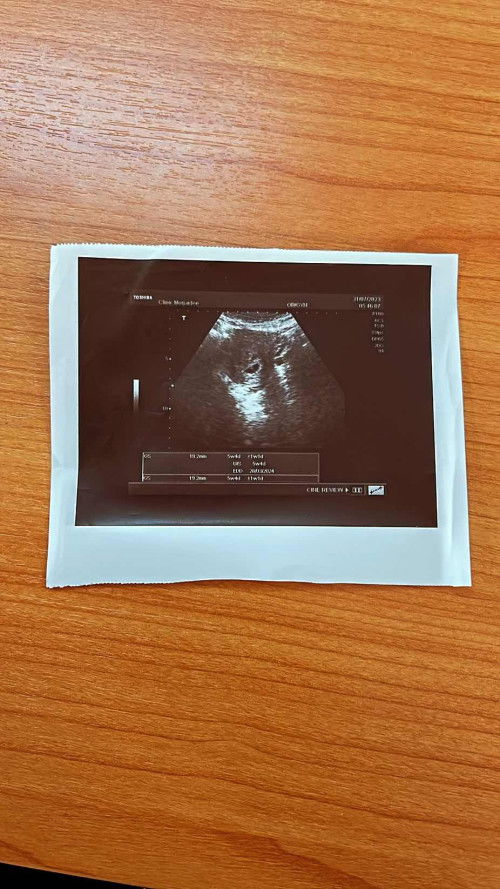

แฝดหรือไม่แฝด

สอบถามค่ะแบบนี้ใช่ถุงตั้งครรภ์2ถุงไหมค่ะ ตอนอุลตร้าซาวด์หมอไม่ได้แจ้งอะไรนอกจากแจ้งอายุการตั้งครรภ์ มีโอกาสได้ลูกแฝดไหมค่ะ